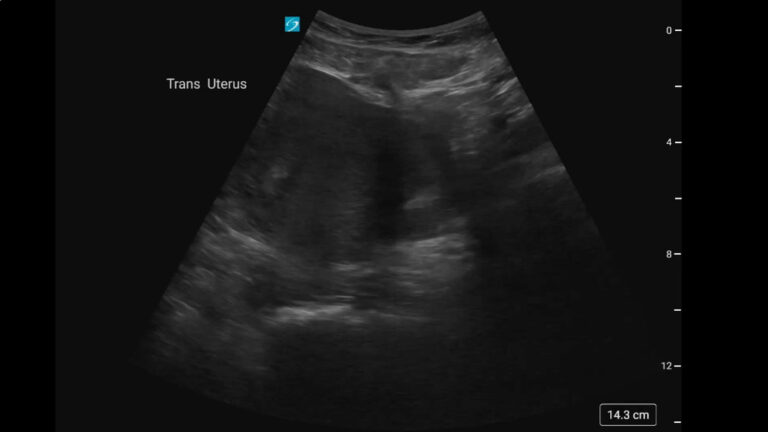

Severe Morning Sickness… or Twins? First Trimester POCUS Pearls